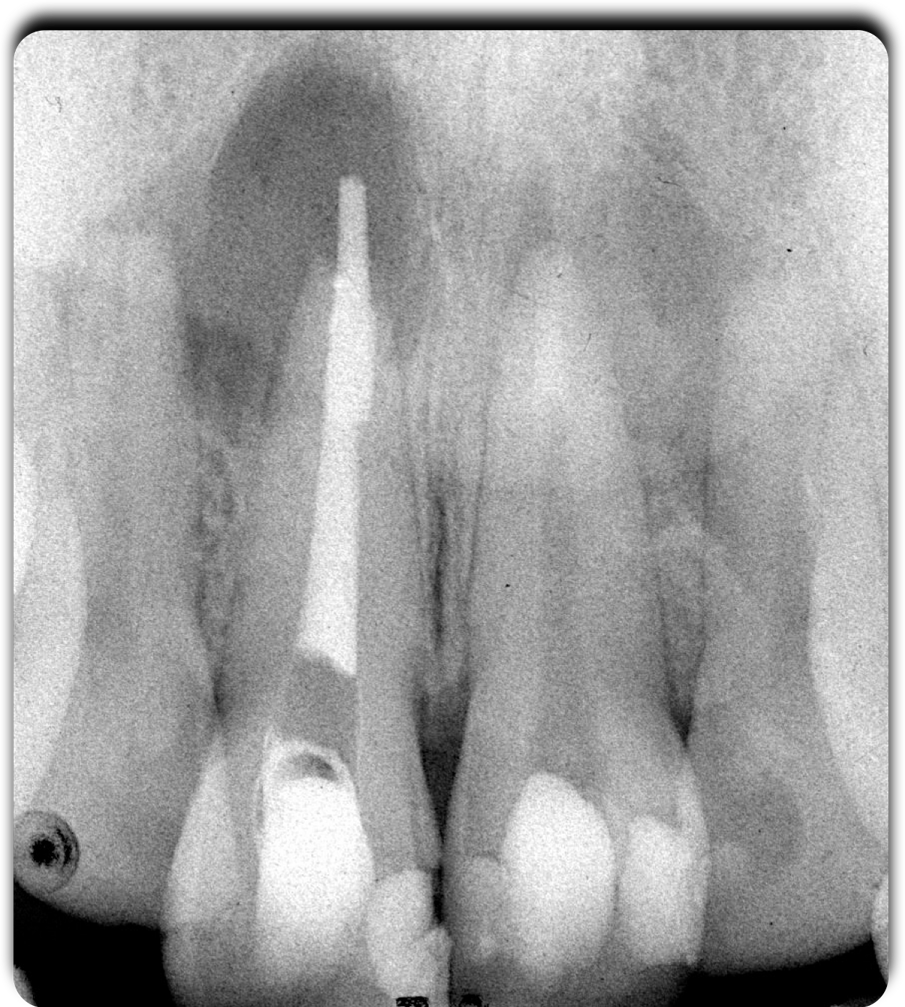

Fig. 3 - Lo stato endodontico iniziale.